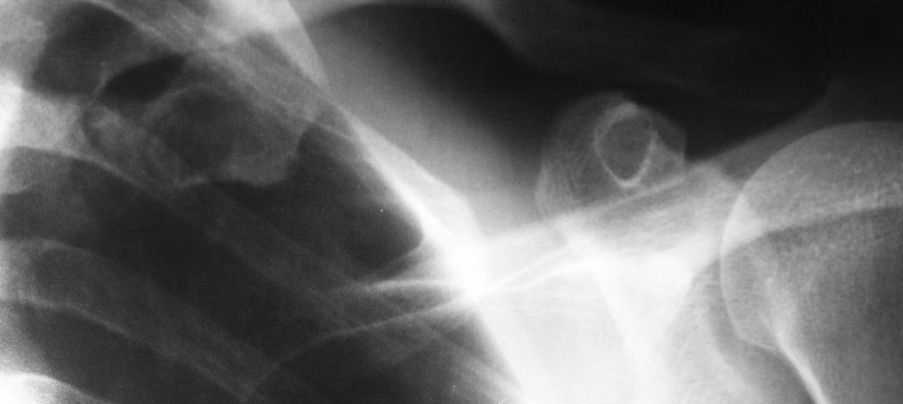

[Ortho] Костная киста первого ребра?

Пациент 42г,больным себя считает около месяца,когда появились боли при

пальпации в области левой подключичной ямки,также беспокоят боли в

области правого плечевого и ключино-акромиального

сочленений.Об-но:пастозность в левой подключичной области,боли при

пальпации там же,кожные покровы физиологической окраски.При осмотре

плечевого сустава -клиника плечелопаточного периартрита.

Приношу извинения за качество рентгенограммы